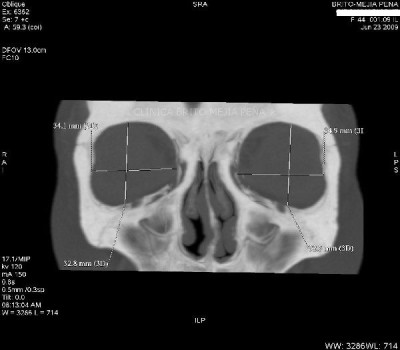

Envíado por BMP Imágenes Diagnósticas

BMP Imágenes Diagnósticas